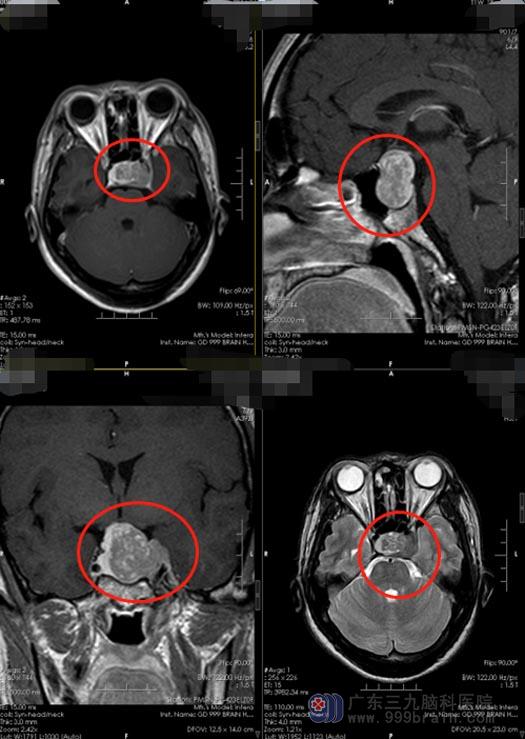

▲术前